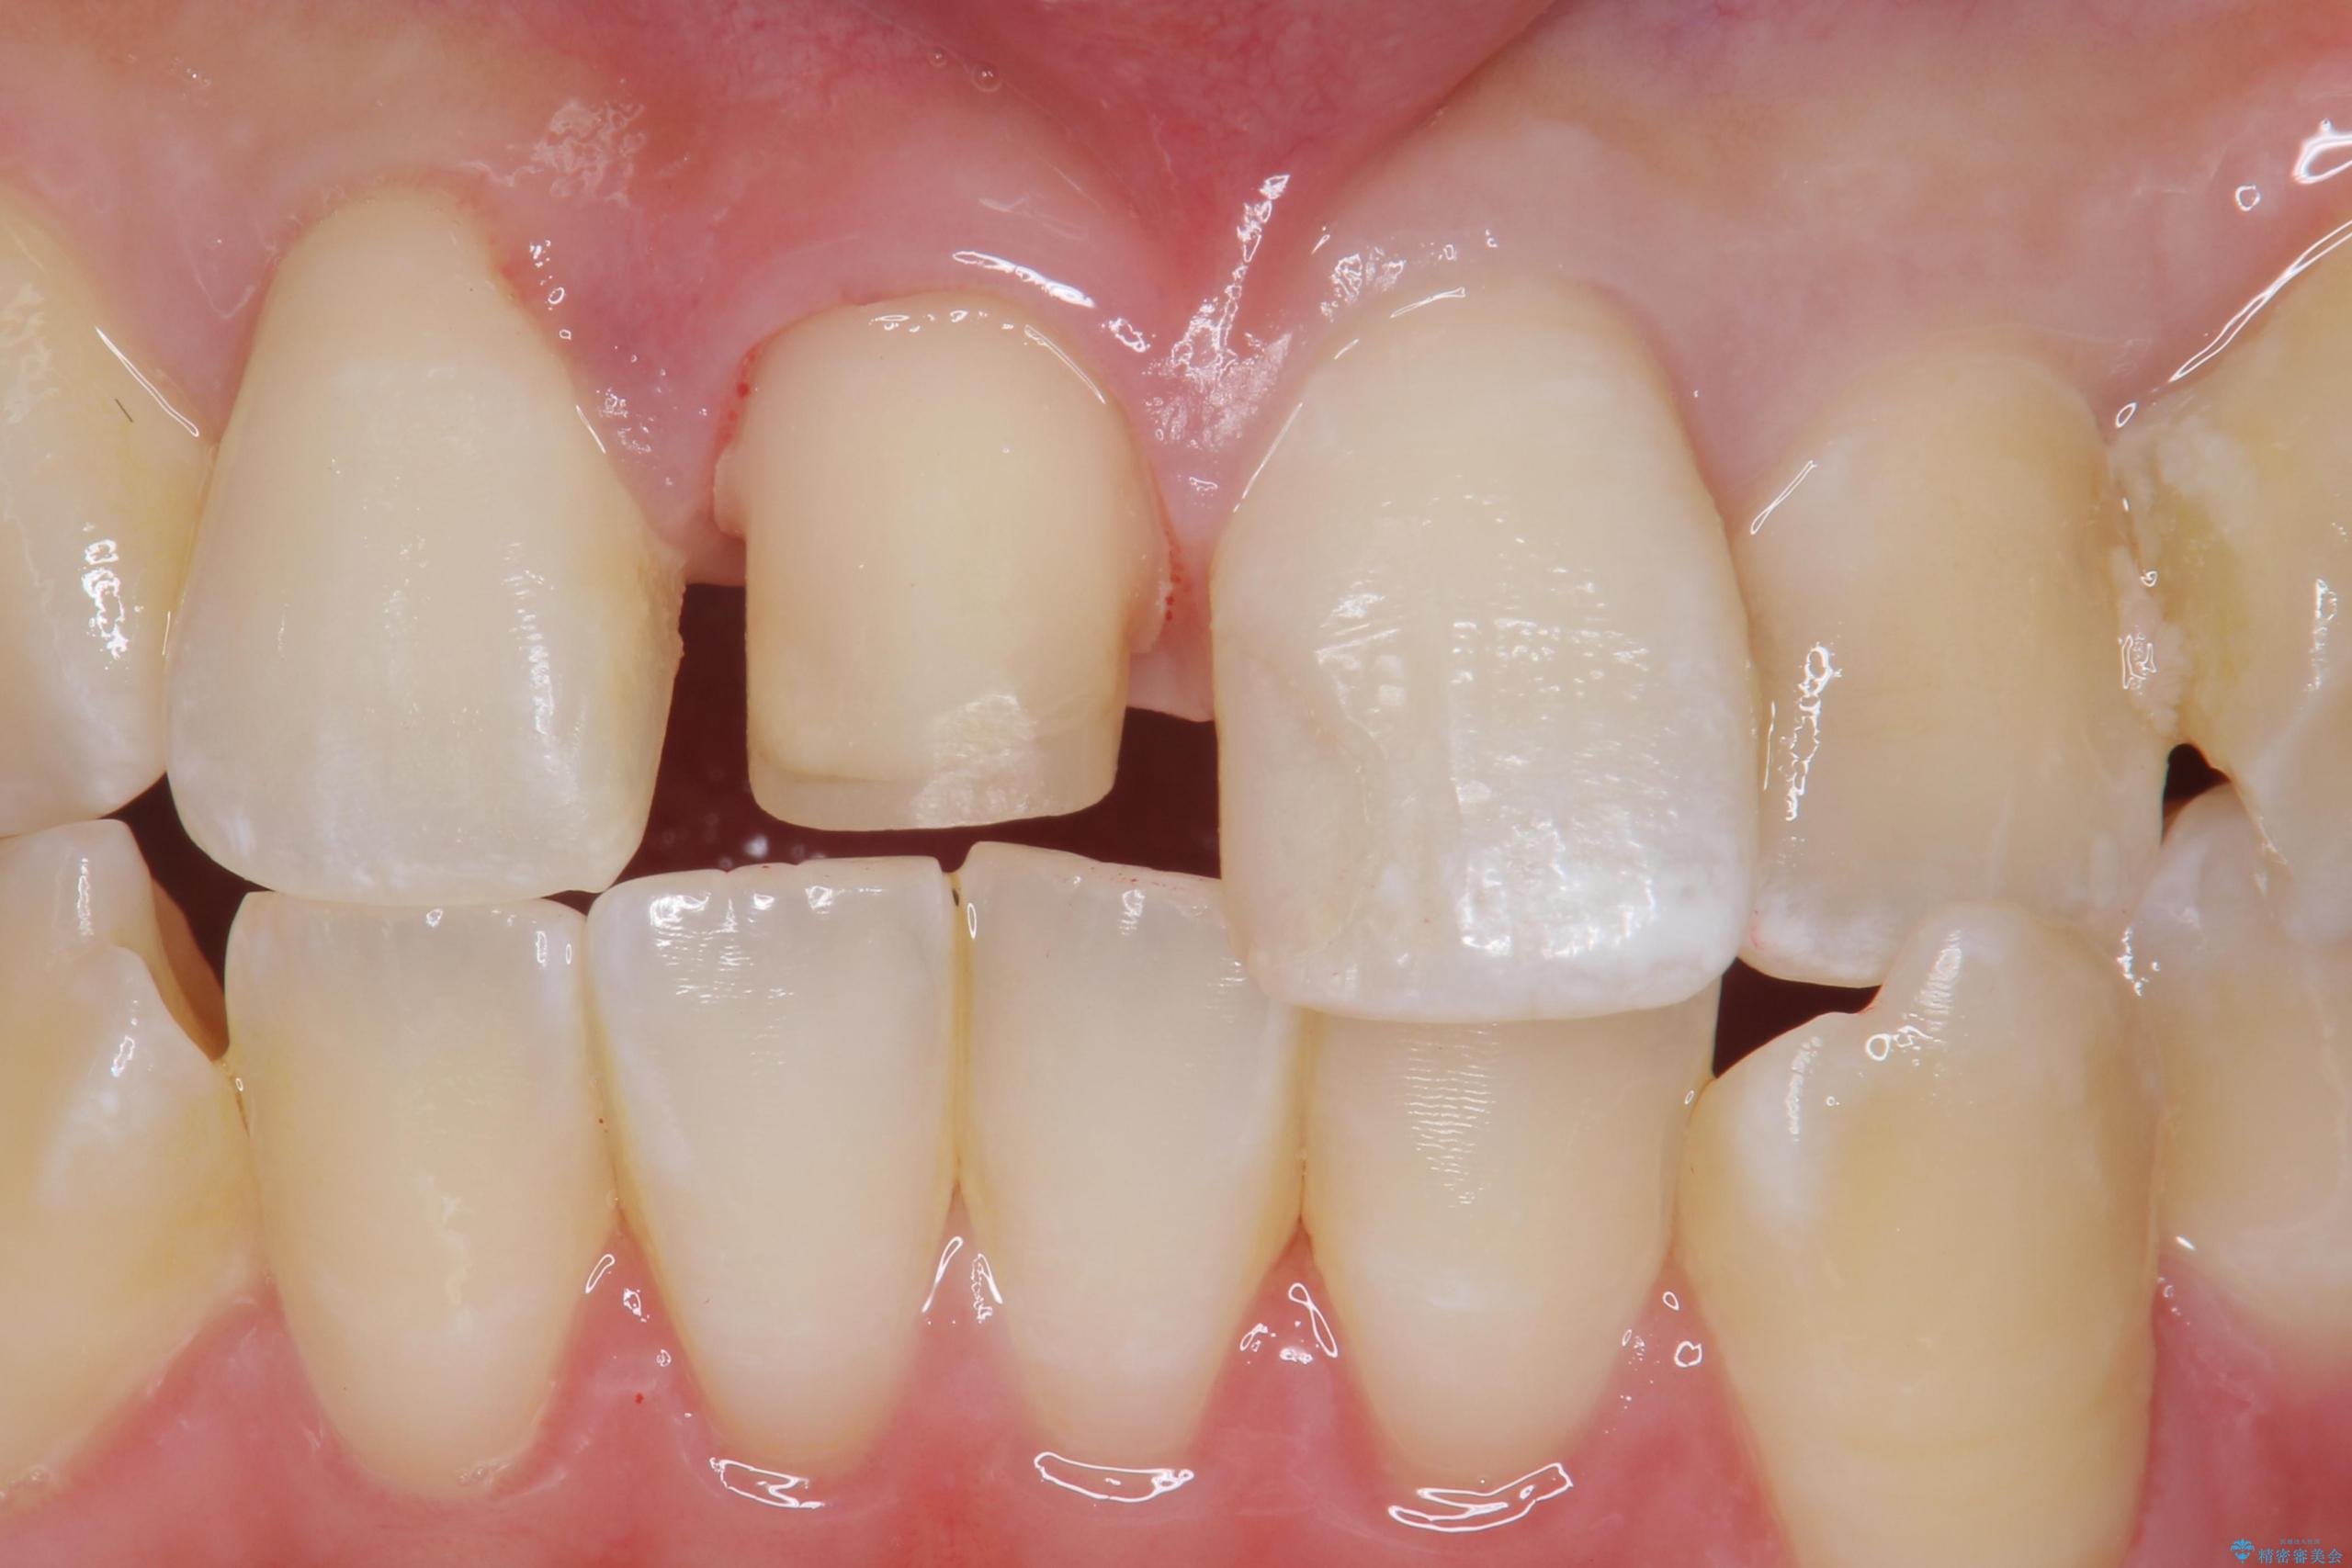

- 前歯のかぶせ物の色が気になるとのことで来院された患者様です。

セラミッククラウンで作り変えていきます。